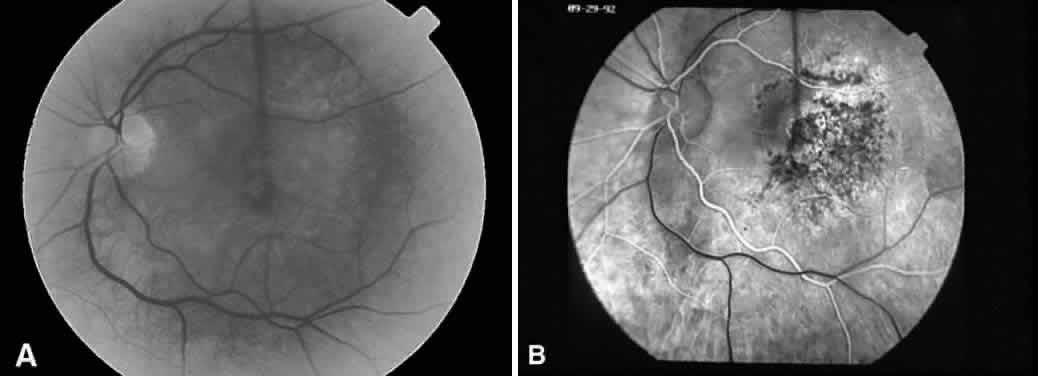

Recognizing light toxicity in the posterior segment may be difficult and is under reported because the findings can be extremely subtle on examination and many cases are asymptomatic. However, clinical features of such lesions are now well described, and when they occur in a high-risk situation, a diagnosis usually can be made. An accompanying fluorescein angiogram (Fig. 2) or visual field test can support a diagnosis if clinical suspicion is high.

Fig. 2. A. Fluorescein angiography of a 49-year-old patient with a malignant melanoma on the left iris who consented to deliberate induction of photic retinopathy by the operating microscope before scheduled enucleation of that eye. Red-free photograph of the normal posterior pole of the left eye pre-exposure. B. Late phase of the angiogram, pre-exposure, demonstrates a normal macula. C. Red-free photograph of the left eye after light exposure showing a vertically oriented lesion centered in the macula. D. Late phase of the angiogram demonstrates hyperfluorescence in the area of photic damage. (Green WR, Robertson DM: Pathologic findings of photic retinopathy in the human eye. Am J Ophthalmol 112:520, 1991)

Clinical correlation between the use of the operating microscope and macular phototoxicity first was suggested in 1977,89 and the first reported cases appeared in the literature in 1983.9,90 Since then, operating microscope-induced retinal injury has become a more commonly recognized clinical syndrome31–38,91–93 and is associated with various anterior (Fig. 3), posterior (Fig. 4), and combined surgical procedures.39–43,94–96 Incidence of reported cases, specifically of iatrogenic causes of retinal phototoxicity, vary between various retrospective and prospective studies.34,38,42,93,97

Fig. 3. A. Fundus photograph of a 58-year-old patient one week after uncomplicated cataract extraction with posterior chamber intraocular lens placement in the left eye utilizing a temporal clear corneal incision. The photograph demonstrates an elliptical area of pigment mottling with a yellow-white appearance at the level of the outer retina (small arrows) and with an overlying neurosensory retinal detachment (curved arrows). B. Red-free photograph of the same patient shows a lighter appearing elliptical area (arrows) at the level of the outer retina. C. Transit phase of the angiogram demonstrates a sharply circumscribed elliptical area of mottled hyper- and hypofluorescence at the level of the retinal pigment epithelium. D. Late phase of the angiogram demonstrates progressive hyperfluorescence and accumulation of dye in the neurosensory detatchment. (Dick JSB II, Bressler SB: Unusual case of postoperative phototoxic maculopathy. The Wilmer Retina Update 4:58, 1998)

Fig. 4. A. Fundus photograph of a patient after macular hole surgery in the left eye. Partial closure of the macular hole resulted in more severe light-induced toxicity temporally where the hole was closed. B. Arteriovenous phase of a fluorescein angiogram of the same patient shows a corresponding area of mottled hyper- and hypofluorescence. (Courtesy of Jay S. Duker, MD, Boston, MA)